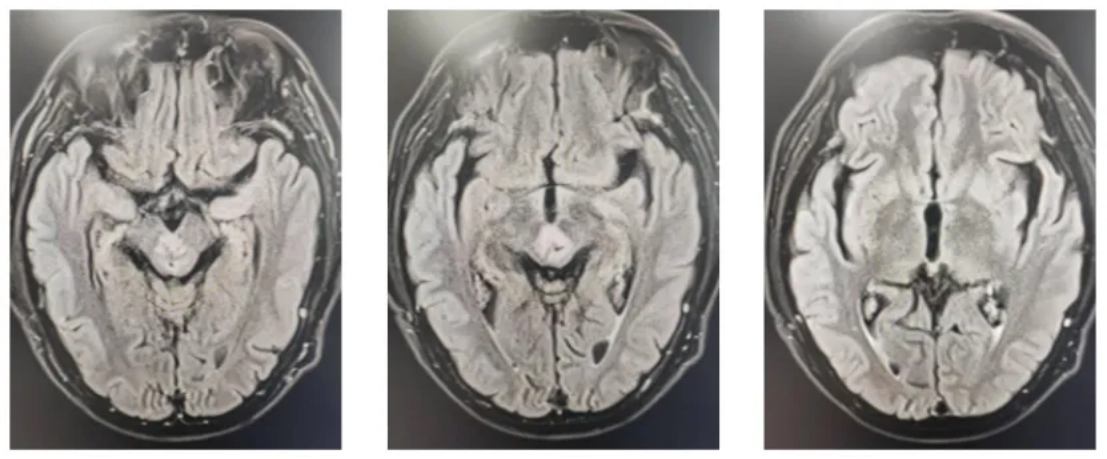

2023-07-25复查颅脑MR:左侧颞叶海马区、左侧丘脑、侧脑室旁条片状异常信号影较治疗前缩小(图2)。

图2 复查颅脑影像学